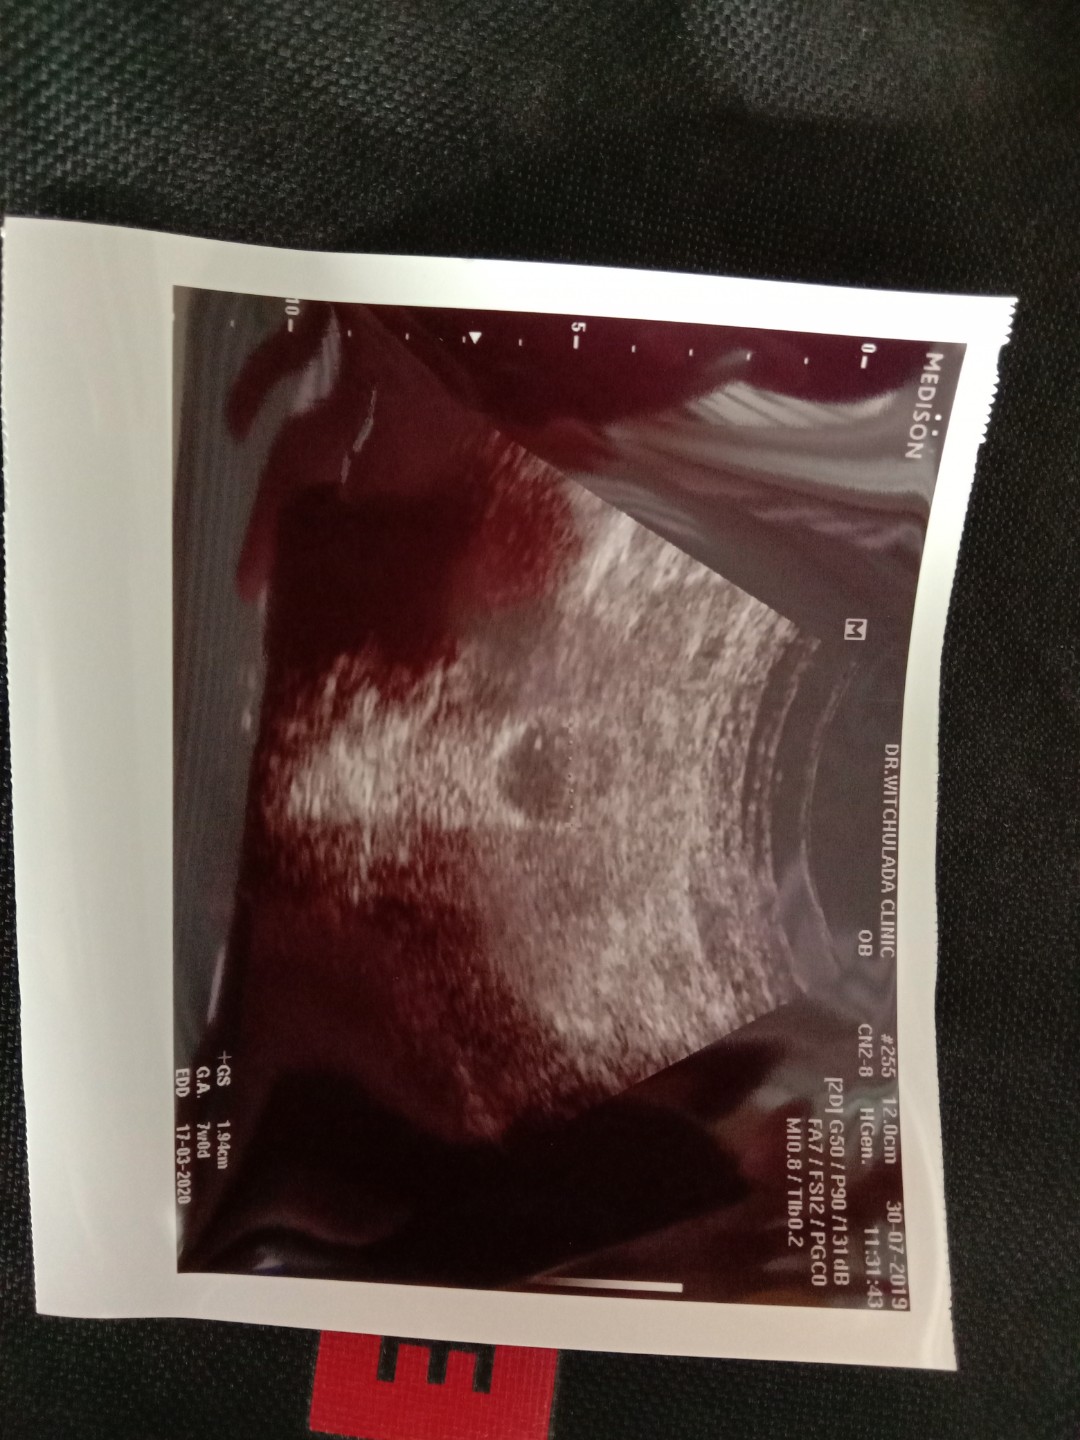

ซาวน์ตอน7w ยังไม่เห็นตัวอ่อน พรุ่งนี้หมอนัดซาวน์อีกรอบ 9w